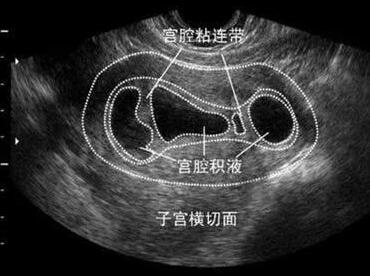

宫腔粘连是由于损伤或感染等原因破坏子宫内膜基底层,使内膜不能自行修复,引起纤维结缔组织增生,造成宫腔各壁相互粘连、宫腔缩窄甚至闭塞。

通常来说宫腔粘连要进行盆腔B超及宫腔镜检查的,还可以做子宫碘油造影检查。B超很好理解,我们重点来说下其他两项 。

1、子宫腔镜检查:可了解有无宫腔粘连,并确定粘连部位、范围、程度及粘连的组织。各组粘连的特点为:子宫内膜粘连与周围的内膜很相似;肌纤维粘连最常见,其特点为有一薄层子宫内膜覆在上面,表面有很多腺体开口;而结缔组织粘连则表面无内膜彤成。